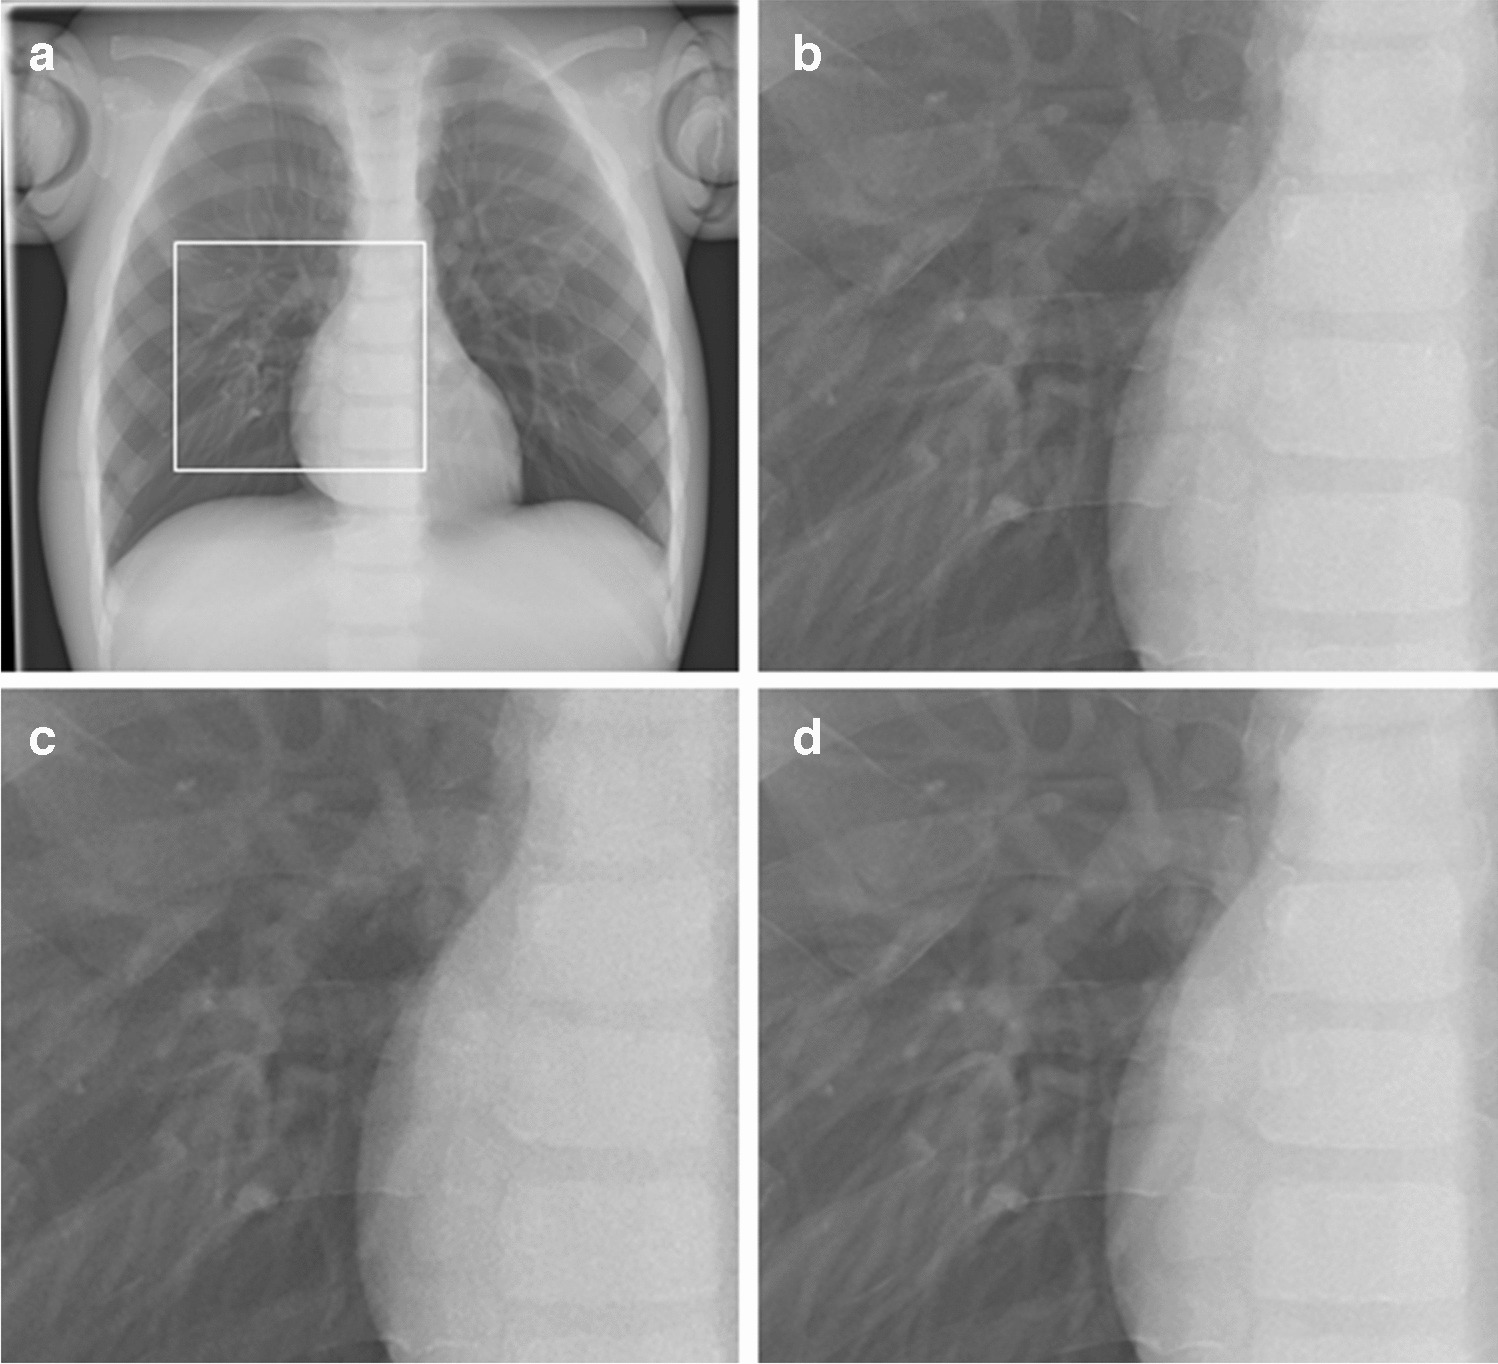

Anteroposterior and lateral images of both phantoms were acquired with the routinely applied digital postprocessing (standard noise reduction) as well as with INR; see examples in Figs. 1 and 2. INR can be applied at a level of 1–10, ranging from the lowest (1) to the highest (10) influence of INR on noise reduction. In this study, a medium level of 5 was used for all images.

Fig. 1

Anteroposterior chest radiographs of the PBU-70 phantom (Kyoto Kagaku). a Dose level 100% with standard noise reduction. The image shows the magnified region in images (b-d) (box). b-d Magnified images at dose level 100% with standard noise reduction (b), dose level 40% with standard noise reduction (c), and dose level 40% with intelligent noise reduction (d)